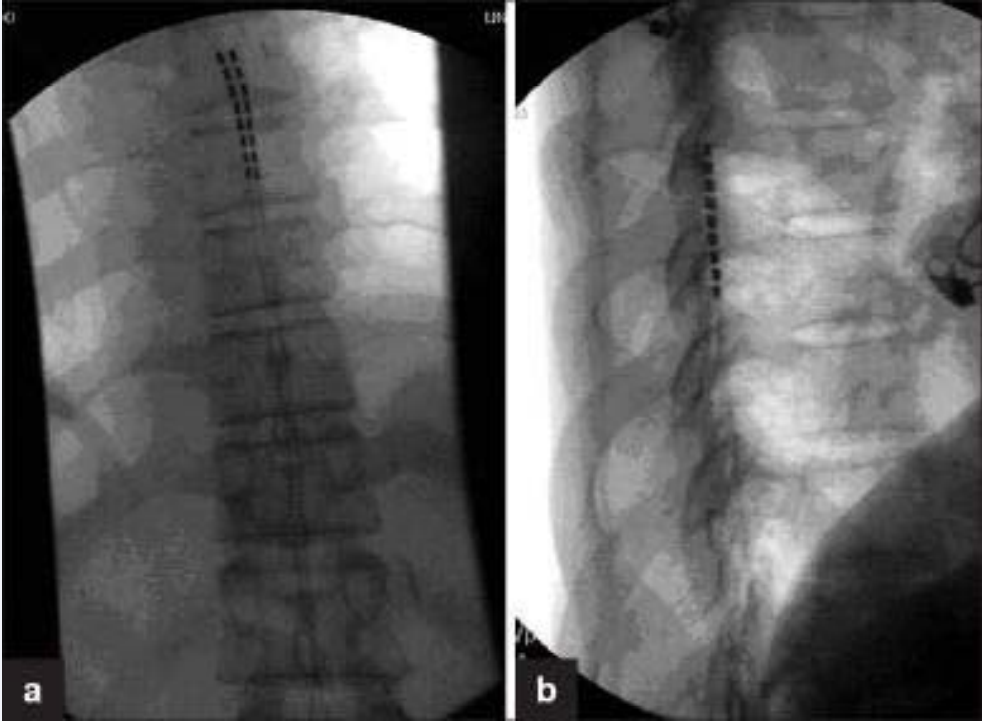

Neuromodulation

The recent advancement in neuromodulation equipment and programming platforms opens the opportunity to use this technology to deal with the chronic pain condition. At present we have to rely on case studies and reported clinical evidence to understand the potential that exists. The majority of the use has being off label use. At present options include the using traditional spinal cord stimulation (SCS) with electrode placement over the dorsal column [36], dorsal root ganglion (DRG) stimulation [37] or peripheral field / plexus stimulation [38] (Figure 4).

Positioning of 2 spinal cord stimulation lead over the dorsal  horn column (2 x 8 electrode)) in the AP and lateral view.

Figure 4: Positioning of 2 spinal cord stimulation lead over the dorsal horn column (2 x 8 electrode)) in the AP and lateral view.

Each case should be evaluated on an individual basis and all the options considered by a pain physician and multidisciplinary team experienced in this area